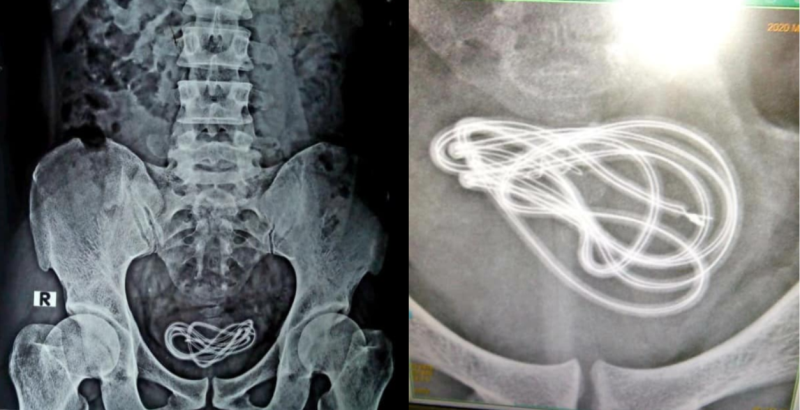

“I operated upon him to find nothing in the gastrointestinal tract, but instead discovered the mobile phone charger cord in his urinary bladder. All of you must be guessing what the entry point and route is.

“It entered through his penile urethra to his urinary bladder. His mental health remains a question.”

He added that the patient initially misled the doctors, claiming to have swallowed the two-foot-long (61 centimetres) cable through his mouth, before scans showed otherwise.

“It’s a type of masturbation called urethral sounding, which is the insertion of an object or liquid into the urethra. The patient had come to us five days after he inserted the cable,” said Dr Walliul.